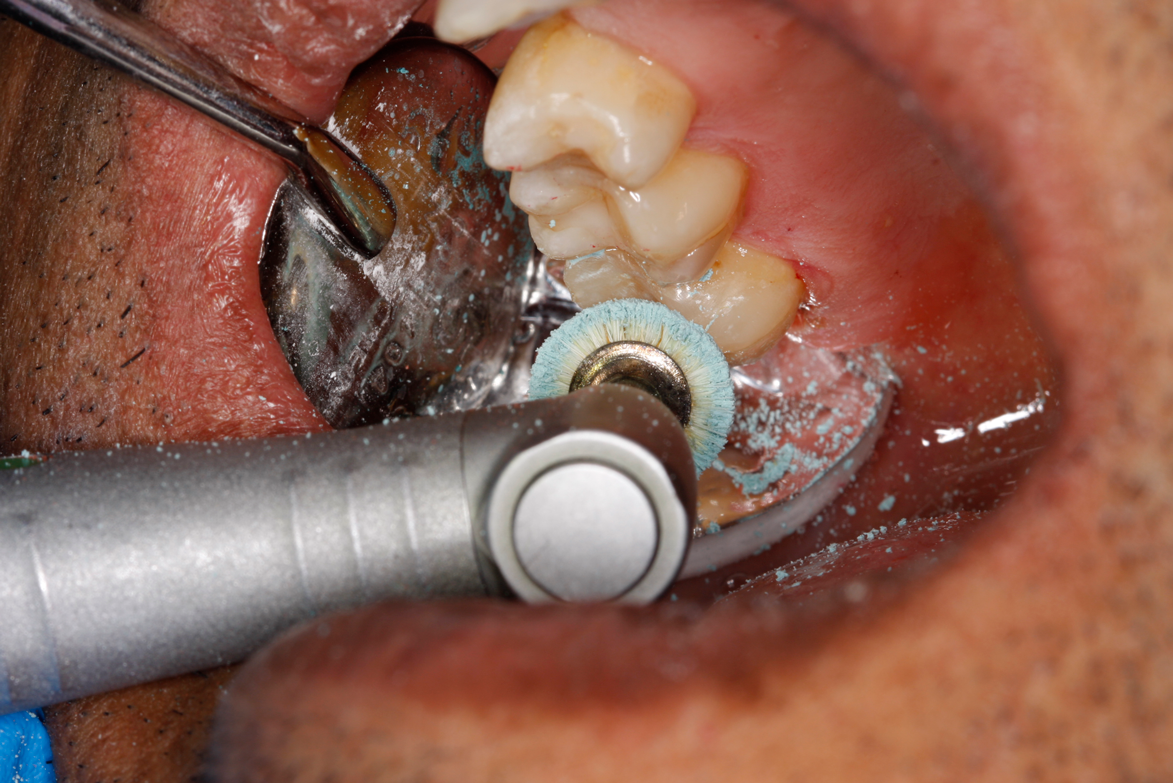

Fig 12. Utilizing particle blasting with a microetcher loaded with potassium carbonate to remove biofilm in the cavity and margins.

Figure 12